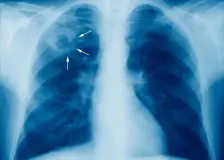

Tuberkulózu šíří v Praze hlavně cizinci a opilci. Léčí je na účet nemocnice

19.března » Metro

Nemoc kdysi zvaná také jako úbytě, souchotiny či bílý mor. Tuberkulóza je stále nejčastější příčinou úmrtí na infekční onemocnění v Česku. Jen načas ji nahradil covid-19. Výrazná část pacientů s tuberkulózou se pak nachází v Praze, kde je nemoc domé…

Problémoví pacienti s TBC – zdroj nákazy, dluhů, někdy i agrese

14.března » Tojesenzace.cz

Nespolupracující nemocní s TBC, dluhy, které po nepojištěných pacientech nemocnicím zůstávají, doplatky za základní léky na tuberkulózu, absence vstupního rentgenového vyšetření The post Problémoví pacienti s TBC – zdroj nákazy, dluhů, někdy i agres…